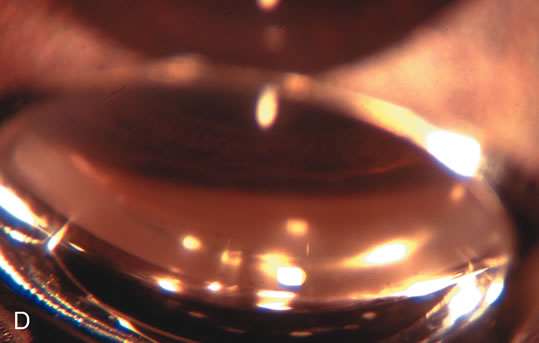

Fig. 4. Viscocanalostomy with deep sclerectomy and phacoemulsification. Nonpenetrating filtration procedures (NPFS) may be combined with phacoemulsification. Patients with mild disc damage and a history of limited topical drug therapy are the best candidates. Patients who require an IOP in the low teens are not good candidates for NPFS. By definition, NPFS is designed to lower IOP without penetrating into the anterior chamber, thereby avoiding the complications associated with trabeculectomy. Viscocanalostomy is intended to allow aqueous to percolate through a trabeculodescemetic membrane into a subscleral cavern created by the deep sclerectomy. The aqueous diffuses from the cavern into the dilated ostia of Schlemm's canal and into the episcleral venous plexus. A. Fashion a uniform 300-micron superficial scleral flap 1 mm into clear cornea. B. Construct a second 600-micron deep flap that facilitates the unroofing of Schlemm's canal, seen as the darker area. C. Use viscoelastic to dilate the ostia of Schlemm's canal. The major problem with viscocanalostomy is the eventual closure of the ostium decreasing flow to the episcleral plexus. D. Dissect the deep flap anteriorly into clear cornea creating the trabeculodescemetic membrane. This membrane is clearly seen between the scleral spur and the bend of the deep flap. The integrity of this membrane ensures the nonpenetrating portion of the surgery. Another problem with NPFS is the eventual fibrosis of this initially transparent membrane requiring goniopuncture. E. Deep sclerectomy gets its name from removal of the deep flap. Removal of this flap creates the potential subscleral space for accumulation of aqueous before it enters Schlemm's canal and exits the episcleral venous plexus. After removal of the deep flap, the superficial flap is sutured into place and conjunctiva closed. Approximately half of these procedures develop a shallow bleb.